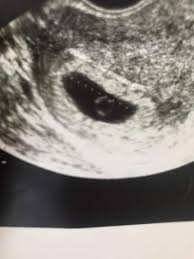

War das erste mal letzten do beim gyn aufgrund eines positiven sst im ultraschall konnte man fruchthöhle und dottersack sehenalles gut sagte sieheute war ich nochmal da also eine woche später56 und man hat im ultraschall nur gesehen das die früchthöhle ne ganze ecke gewachsen ist und das der dottersack zu sehen istsie vermutet am dottersag minimale embryonale anlagen aber ist. SSW 55 Ultraschall keine Fruchthöhle. War am 247.

Ultraschallbild Fruchthöhle 5 SSW 3 Beitrag 6 Erstmal herzlichen Glückwunsch zur Schwangerschaft. Allzu viel wirst du auf dem Monitor nicht erkennen können aber bei einer Ultraschalluntersuchung kann ab der 4. Ssw nachdem sich in der 1.

Man konnte nur eine leere fruchthöhle erkennen. Frauenarzt Termin laut Ultraschall bin ich ssw 55 wobei allerdings nur eine leere fruchthöhle zu sehen war von 095cm. Ich habe eine kurze Frage.